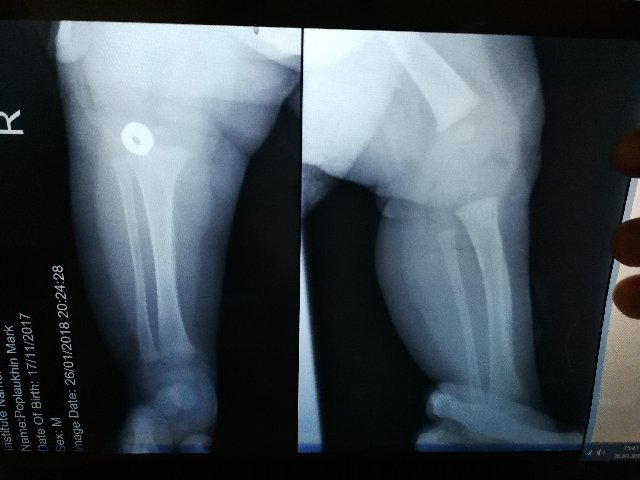

Гиперостоз на месте, искривление голени присутствует, но уменьшается. Ребенку не мешает. В тот раз не приложились снимки, прикладываю для истории снова.

Слева легкий вальгус. Сохраняется зажимание указательных пальцев, особенно слева, в играх на мелкую моторику.  Учу контролировать. Все равно предпочитает правую сторону.